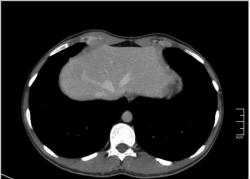

КТ печени. Наблюдения для размышления.

Уважаемые коллеги, особенно врачи КТ. Надеюсь что данная публикация окажется полезной для многих из Вас. Ниже представлены сканы печени; предлагаю Вам ознакомится с ними и высказать свое мнение. Пациент мужчина средних лет, специфичных жалоб не предъявляет.

Уважаемый v1tal! Огромная Вам благодарность; Вы назвали ключевое слово: фаза! Высказанная Вами мысль, это моя основная цель данной публикации. Постараюсь позже более детально объяснить почему. Представленные сканы выше, были выполнены на стандартной портальное фазе. А сейчас, я покажу сканы данного пациента выполненные на артериальной фазе :

Да Ola la, Вы абсолютно правы; это Фокальная Нодулярная Гиперплазия печени (FNH Focal Nodular Hyperplasia). Одна из немногих гиперваскулярных опухолей печени. Наверное некоторые коллеги спросят, и зачем было изначально публиковать портальную фазу, на которой «не видно» (хотя опухоль видна, пусть и не напрямую, и Nela это доказала); и только потом показывать сканы на артериальной фазе, на которой всё «красиво и показательно». Постараюсь объяснить.